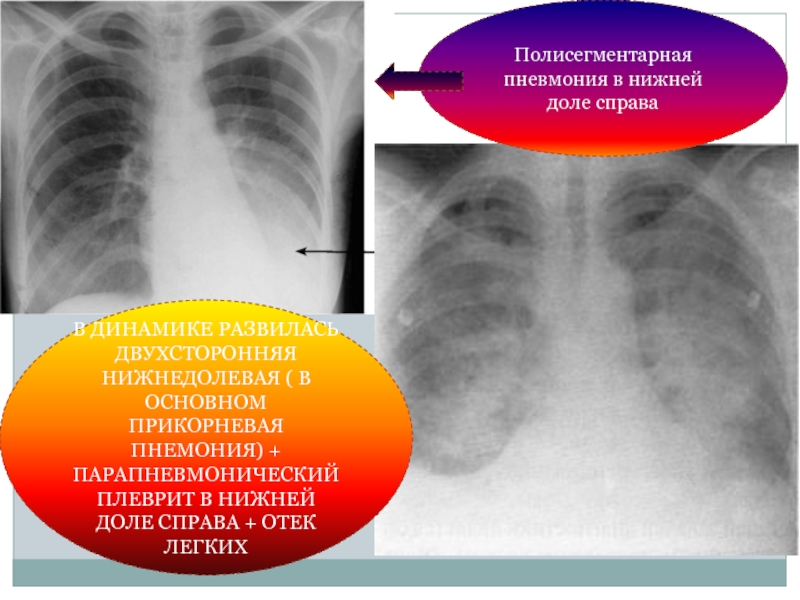

Острая внебольничная пневмония по МКБ-10: признаки и примеры